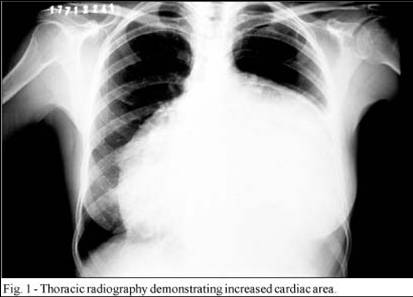

weekly clinical round for undergraduate from 8 to 11 AM during which interpretation of CHEST X rays was done for all cases of cardiothoracic surgery, gived by 2 staf member for 3 months